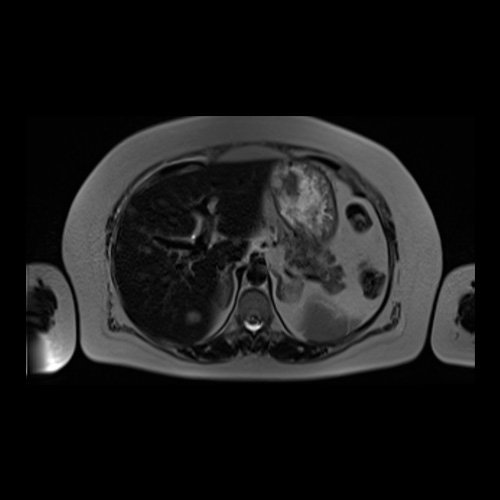

• RMI abdomen y pelvis con contraste EV (14/02/26): En las bases pulmonares se visualizan atelectasias laminares bibalsales. No se identifica derrame pleural. El hígado es de forma, tamaño y situación normal. La superficie es lisa, los bordes son agudos. Se observan múltiples lesiones sólidas de distribución difusa, levemente hiperintensas en T2, con restricción en difusión y realce homogéneo tras la administración de contraste EV, la de mayor tamaño de 15 mm en segmento VII. Sugiero conocimiento histológico. La vía biliar intra y extrahepática es de calibre conservado. La vesícula biliar es de forma y situación habitual, sus paredes son finas y no presenta imágenes hipointensas en su interior, que sugieran la presencia de litiasis. El bazo es de forma, tamaño y situación normal, sin efectos de masa focales. El páncreas es de forma, tamaño y situación normal, sin efectos de masa. El Wirsung es de calibre conservado. Glándulas adrenales de forma, tamaño y situación normal, sin efectos de masa. Ambos riñones son de forma, tamaño y situación normal, con adecuada diferenciación córtico subcortical. No se observan alteraciones a nivel de la vía excretora. No se observan adenomegalias retroperitoneales ni intraperitoneales. La aorta abdominal, las arterias iliacas primițivas, internas, externas y femorales son de trayecto y calibre normal La vena cava inferior, las venas ilíacas primitivas, internas, externas y femorales son de trayecto y calibre normal. No impresionan alteraciones a nivel del tracto gastrointestinal. La vejiga es de paredes finas, normalmente distensibles, sin evidencia de lesiones endoluminales ni parietales. Mioma transmural en hoja anterior de útero que mide 55 x 47 mm sin signos de complicaciones. Imagen ovalada de contenido líquido que mide 65 x 52 mm en el espesor del tejido celular subcutáneo de región antero-superior de muslo derecho, por delante de músculo sartorio, que no presenta realce tras la administración de contraste EV.

RMN de abdomen con contraste endovenoso (14/02/26)  Corte axial (T2): múltiples lesiones sólidas de distribución difusa, levemente hiperintensas.

RMN de abdomen con contraste endovenoso (14/02/26)  Corte coronal (T2): adenoma suprarrenal izquierdo; lesión hepática redondeada hiperintensa redondeada en segmento VII.